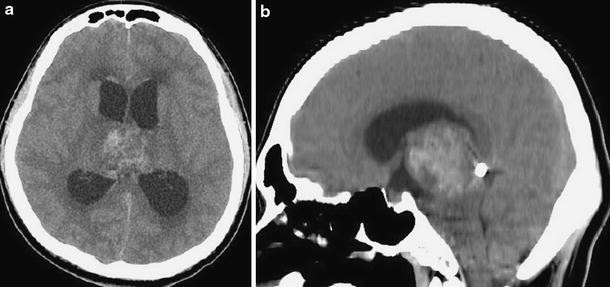

A 23-year-old man was transferred to our department because of progressive consciousness disturbance. He was drowsy on admission. A CT scan revealed a well-demarcated and heterogenous mass with calcification in the pineal region. The mass was approximately 40 mm in diameter, and extended into the lateral ventricles, causing obstructive hydrocephalus (Fig. 1). Based on the CT scan, a non-germinomatous germ cell tumor was suspected. The patient developed Cushing’s sign soon after admission. A neuroendoscopic biopsy was conducted for the lesion and ventriculoperitoneal (VP) shunting was performed. Endoscopic third ventriculostomy was not selected because the third ventricle was filled with the tumor. The lesion was reddish in color; histological diagnosis of the biopsy specimen was germinoma. Serum AFP concentration was 7.4 ng/ml (normal <10 mg/ml). HCG level was 4.6 mIU/ml (normal <1.0 mIU/ml), and HCG-β level was ≤0.1 ng/ml. In the cytological examination of cerebrospinal fluid, tumor cells were not detected. His consciousness disturbance persisted after the surgery. Although he subsequently underwent focal irradiation (20 Gy), the tumor enlarged. Two weeks after presentation, during irradiation, he developed deep venous thrombosis and pulmonary embolism. A filter was placed in the inferior vena cava and anticoagulant was administered. Systemic CT scan did not show abnormal mass lesions except for venous thrombosis. Three weeks after presentation, partial resection was carried out via an occipital interhemispheric transtentorial approach. Histological diagnosis was mature teratoma. The germinomatous component was not identified. Tumor enlargement during radiation was considered to be “the growing teratoma syndrome”. Whole-brain irradiation (24 Gy) was administered postoperatively. After tumor resection and irradiation, serum AFP concentration was to 2.4 ng/ml and HCG level was <1.0 mIU/ml. Three months after presentation, subtotal removal was carried out via an anterior transcallosal transchoroidal approach. The shunt system was also removed, because obstructive hydrocephalus improved. Histological diagnosis was mature teratoma without a germinomatous component. Serum AFP concentration was 1.5 ng/ml and HCG level was <1.0 mIU/ml after subtotal resection. In a series of cerebrospinal fluid examinations, tumor cells were not detected. The residual lesion was controlled (Fig. 2). His consciousness disturbance failed to improve, and he was bedridden.

Fig. 1

Initial plain CT scans (a axial image, b sagittal image) showing a mixed density mass with calcification in the pineal region and hydrocephalus